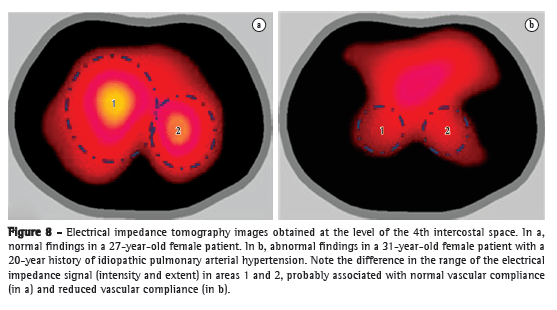

Regional changes in blood flow can be visualized by EIT in two ways. The first, which is based on the indicator dilution technique, involves the use of an electrically conducting fluid as contrast material, similarly to CT and MRI studies. The second approach analyzes the changes in the lung parenchyma impedance resulting from the change in systolic volume during the cardiac cycle, cycle by cycle. Coupling of image acquisition with the R-wave on electrocardiogram (the ECG-gated technique) filters ventilation-related fluctuations, obtaining only those that are due to circulation. The resulting image is likely to reflect pulmonary circulation pulsatility or distensibility.

An excellent model of disease in the pulmonary microcirculation is PAH, in which vascular remodeling directly affects the distensibility properties of microcirculation. When vascular compliance is reduced, with consequent accommodation of lower volumes, the electrical impedance change in PH is likely to be decreased as well. In one study,(59) EIT was used in patients with PH for determining vascular response to vasodilator testing with epoprostenol during invasive hemodynamic assessment. Of the 8 patients evaluated, 7 did not meet the vasodilator response criteria, EIT showing no impedance change in those 7. In the lone responder, the increase in impedance change was found to correlate strongly with decreases in mPAP and pulmonary vascular resistance, regardless of the increase in systolic volume. In another study,(60) the differences in the impedance of the pulmonary circulation were analyzed in 21 patients with idiopathic PAH (IPAH) and 30 healthy subjects. The authors observed a reduction in impedance change in the IPAH group, which provides support for the use of EIT in the assessment of the pulmonary circulation and of PH.

In Brazil, a 32-electrode EIT scanner is being developed for the assessment of lung perfusion. In the context of IPAH, the images obtained with this new scanner (Figure 8) are encouraging, demonstrating not only a reduction in electrical impedance, as in the two aforementioned studies, but also a change in the impedance wave morphology, which might correlate with the pulse wave of the pulmonary circulation.